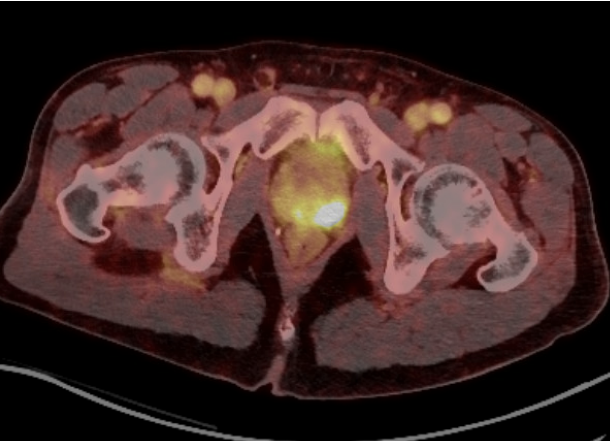

He underwent a transperineal MRI/US fusion-guided biopsy under local anesthesia, reporting a pain score of 1 out of 10 on the visual analogue scale (VAS). His prostate biopsied revealed Gleason 4+3 disease in all four targeted cores of the MRI region of interest. He underwent a PSMA PET/CT which revealed no evidence of metastatic disease, but was concerning for direct invasion of the left seminal vesicle (Figure 2).